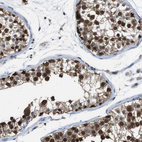

Immunohistochemical staining of human testis shows strong cytoplasmic positivity in cells in seminiferous ducts.